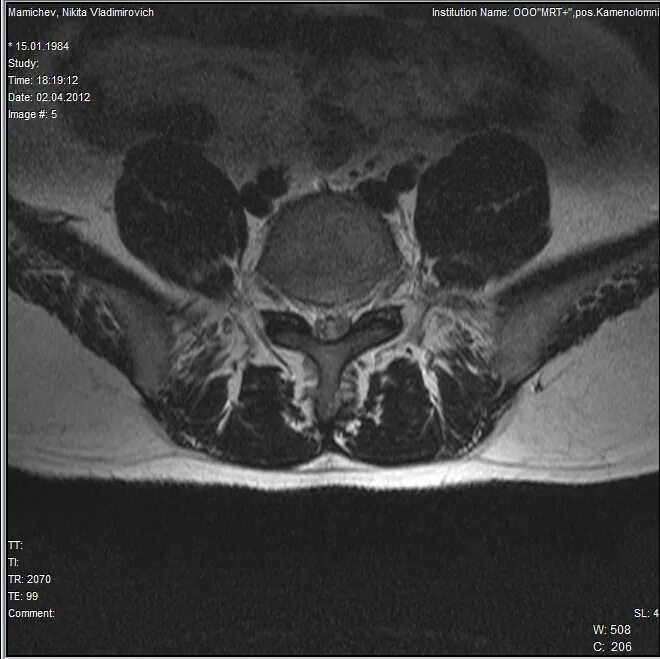

Диффузная грыжа l4 l5